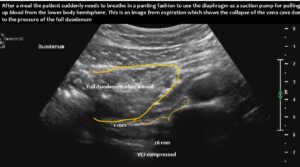

Immediately after food was taken up, the stomach pumped it into the duodenum, which subsequently enlarged and compressed the vena cava.

This suddenly interrupted or massively compromised the venous return from the lower body hemisphere. This led to a sudden drop in the circulating blood volume. Due to reduced lung perfusion as a consequence of the reduction in central flow volume, panting developed to enhance oxygenation of the remaining small blood volume. At the same time, the reduced blood flow to the brain, in combination with hypocapnia as a result of hyperventilation to fight imminent compromise of oxygenation, caused dizziness and a sensation of near fainting.

Functional ultrasound can demonstrate the entire pathophysiological chain, from underlying lordosis to postprandial duodenal enlargement and subsequent vena cava compression, especially when standing after eating.